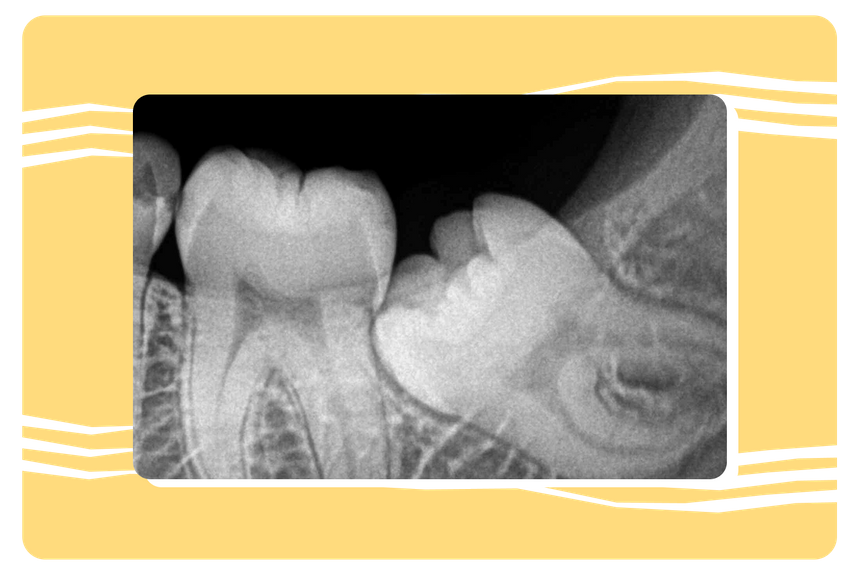

4. Зубы мудрости

Что это

Задние коренные зубы (моляры), которые прорезываются последними — обычно между 17 и 25 годами. В стоматологии и в народе их называют «восьмерками».

Зачем требовались

Нашим предкам с крупными челюстями эти зубы помогали пережевывать жесткую растительную пищу, богатую клетчаткой. Такая диета требовала больше жевательных усилий и огромную челюсть.

Что с ними стало сейчас

У современных людей челюсть уменьшились в ходе эволюции, а пища стала более мягкой и простой, поэтому необходимость в дополнительных зубах отпала сама по себе. У владельцев «восьмерок» они часто вызывают проблемы — воспаления и даже смещение зубного ряда.

Примерно у 35% населения зубы мудрости не прорезываются вообще. Это называется агенезией, то есть таким состоянием, при котором какой-либо орган не формируется должным образом во время внутриутробного развития.